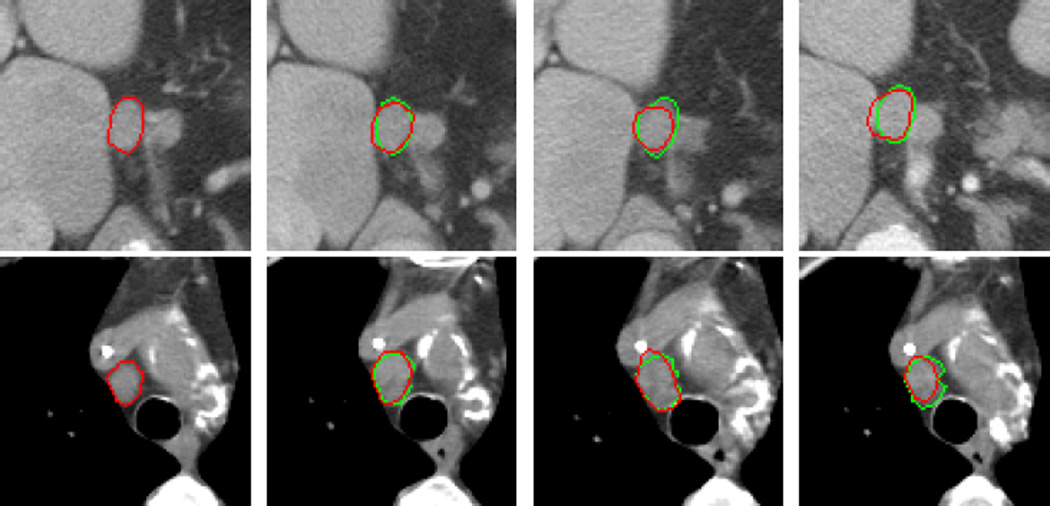

Fig.7 shows the automated segmentation results of Fig.2, where the red curve in Fig.7(a) is the hand-drawn circumscription of the lymph node in the baseline image, showing that the snake model can precisely segment the strong object edges and smoothly estimate the weak or lost object edges.

Fig.7.

Automatic segmentation results of Fig.2. The green and red curves in the follow-up images ((b)–(d)) are the gold standard and the automatic segmentation results with our algorithm, respectively.

Fig.8 shows the effect of the snake model. Depending on the internal forces of the snake model, the segmentation results with the snake model (the second row) are smoother than without the snake model (the first row). The smoothness is suitable with the lymph node characteristics. The image gradient based external force of the snake model can make the initial evolving curve closer to the object boundaries.

Fig.9 shows the segmentation results from four image series. The image density difference in some parts of the lymph node boundary is small, because the lymph nodes are connected with the tissues that have similar pixel values. The similarity distance based on image patch described in Section 3 can enlarge the difference between the lymph nodes and the surrounding tissues.

Fig.9.

Segmentation results in four image series